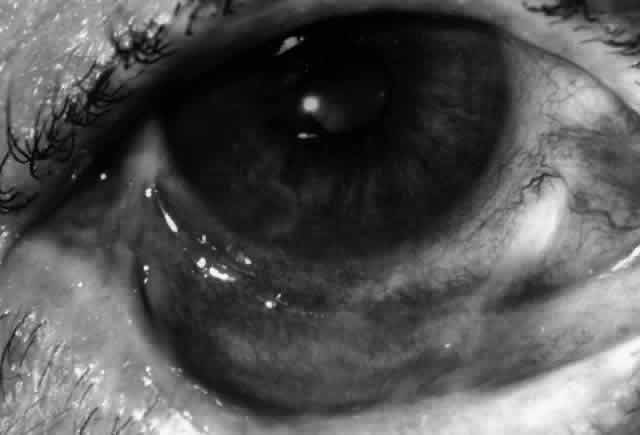

Clinically, the ocular disease in cicatricial pemphigoid (OCP) may present unilaterally in the form of a chronic, recurrent catarrhal conjunctivitis, but it eventually becomes bilateral. Subepithelial fibrosis is characteristic of stage 1 of OCP (Fig. 7). Stage 2 shows fornix foreshortening (Fig. 8), and symblepharon formation is the hallmark of stage 3 (Fig. 9). Stage 4, end-stage disease, is characterized by ankyloblepharon and surface keratinization (Fig. 10). Obstruction of the lacrimal ductules and meibomian gland ducts eventually produces an unstable tear film and progressive sicca syndrome, but it is to be emphasized that OCP is not a dry-eye syndrome until late in the disease course.20 Trichiasis and entropion occur because of the subepithelial fibrosis, with eventual keratopathy, corneal neovascularization, and corneal ulceration and scarring.20

Fig. 7. Stage 1 cicatricial pemphigoid, with cicatrizing conjunctivitis, and fine striae-type areas of subepithelial fibrosis, but without evidence of shrinkage of the conjunctiva.